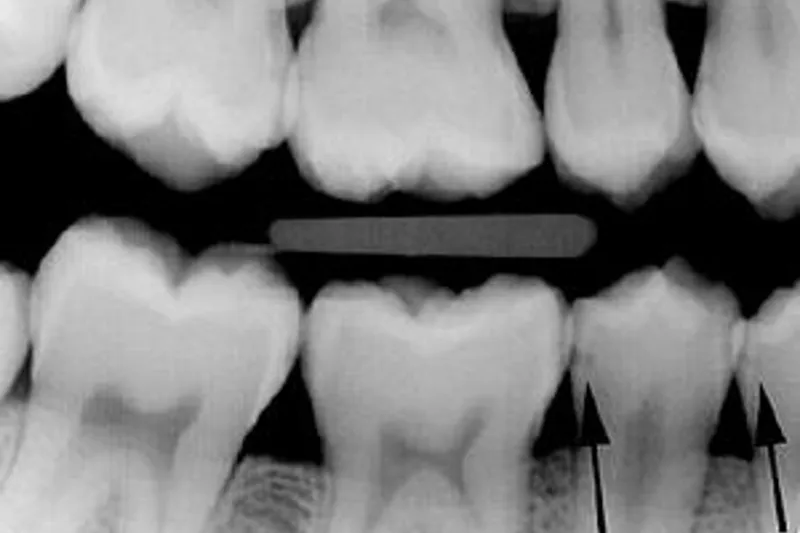

Forskere fra Odontologisk Institut, Københavns Universitet, har undersøgt anvendeligheden af to nyere metoder, impedansspektroskopi (IS) og laserfluorescens (LF), i diagnostik af okklusal caries. IS (CarieScan PRO) og LF (DIAGNOdent pen) blev sammenlignet med bite-wings og visuel registrering efter ICDAS-kriterierne.

54 % af tænderne var helt sunde eller havde lette forandringer (ICDAS-score 0-2), mens 46 % havde moderate eller omfattende læsioner (ICDAS-score 3-5). Med den visuelle registrering som reference viste de tre øvrige metoder varierende resultater. IS havde høj specificitet, men desværre en meget lav sensitivitet, mens LF havde moderat høj specificitet og sensitivitet. Bite-wings havde moderat specificitet og høj sensitivitet og kom samlet set ud som den bedste metode med en diagnostisk odds ratio på 25,0 mod 13,5 for IS og 5,4 for LF.